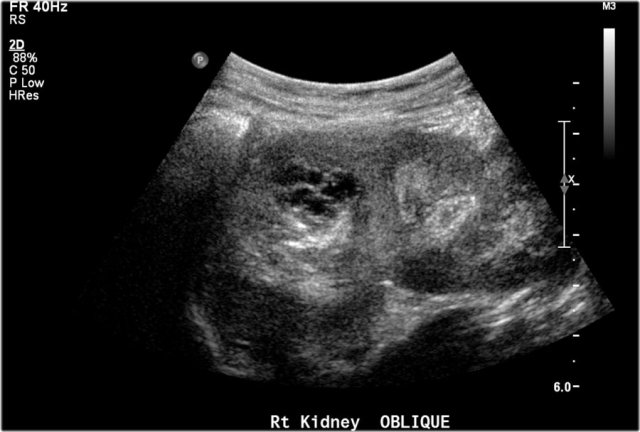

One-year-old boy was referred with a diagnosis of a cystic nephroblastoma.

Ultrasound detected a huge cyst in the middle of the abdomen.

When examined from the left flank with a high frequency linear array probe some parenchymal tissue was visible surrounding very dilated calyces. This is compatible with an extreme hydronephrosis.

At first it was thought that there were some solid parts in the cyst.

But when pressure was applied with the probe this proved to be debris.

MRI depicts the hydronephrosis with more overview.

The cause was a pyeloureteric stenosis.

The left kidney had 33% split renal function on renography.

A pyelum reconstruction was successfully performed.